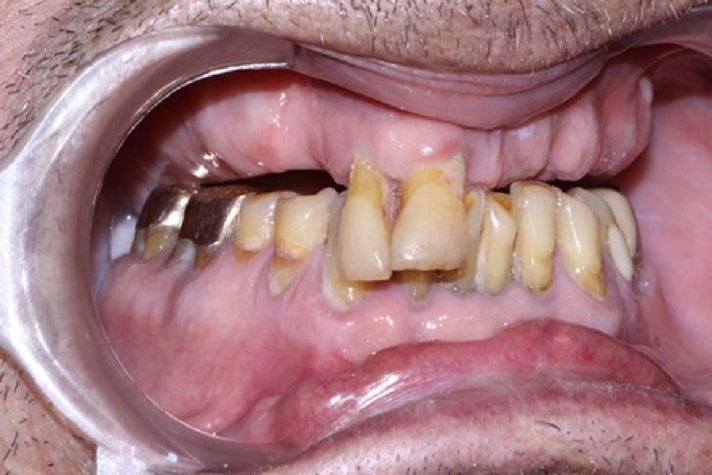

Tall and Tilted Pin Hole Immediate Loading ( TTPHIL) is a modern and most reliable technique for dental implantation. The special feature of such method is that dentist combine long and wide implants with bi-cortical support bone.

The All on 6 and All on 4 technique apply that method of implants placement.

This technique also use immediate loading so the implants are placed right after teeth extraction.

This case report show the successful All on 6 dental implantation using Alpha Dent implants.